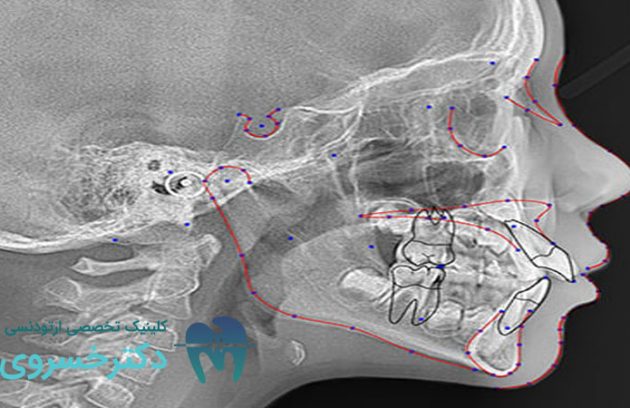

تشخیص ارتودنسی به صورت فردی